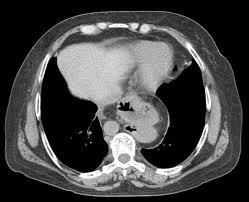

A Large Intra Abdominal Hiatal Hernia As A Rare Cause Of Dyspnea